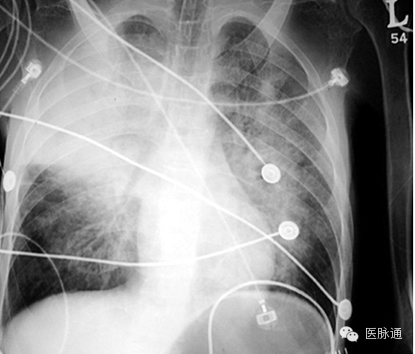

急性呼吸窘迫综合征定义为急性起病,PaO2/FIO2≤200 mmHg,胸片双侧浸润,以及肺动脉楔压≤18mmHg或无左心房高压的临床征象。胸片最常见的表现为双侧非对称性实变伴支气管空气征象(如图8箭头所示)。间隔线和胸腔积液并不常见。渗出期的早期表现是掩盖肺血管纹理的双侧实变。这些病变可演变为典型非对称的更广泛的弥漫性实变。在随后的纤维化阶段可能形成弥漫性间质。存活患者子啊10-14天后,多数影像学异常表现开始消散。

图8